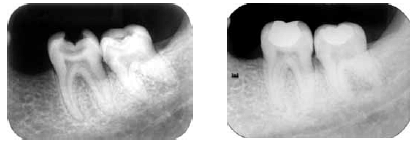

Julgue os itens a seguir acerca das radiografias acima, que mostram a preservação, após dois anos de um tratamento.

A câmara pulpar do dente 38 reduziu de tamanho.